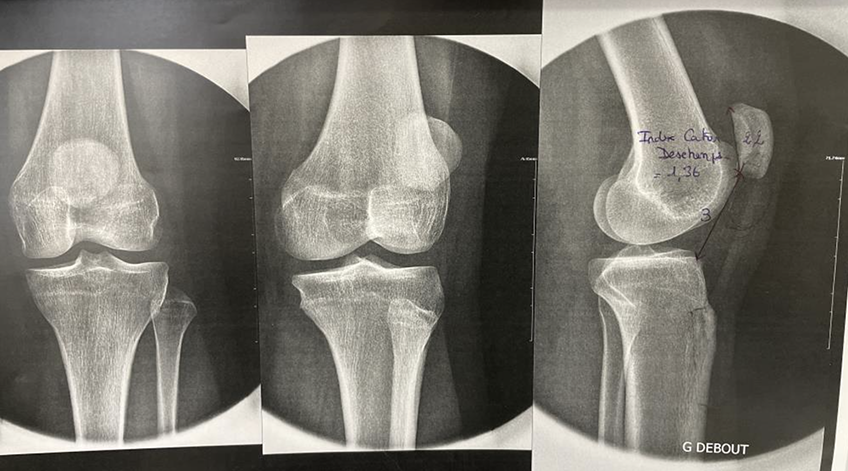

Jeune patiente qui présente une patella alta (ou rotule haute) entrainant un problème d'engagement de la patella - Dr Dumoulin

Radiographie qui retrouve une consolidation de l'ostéotomie avec correction de la hauteur de la patella - Dr Dumoulin